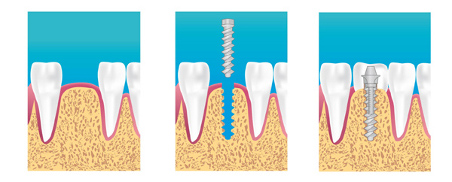

Un implant est une sorte de vis en titane, fixée dans l'os comme la racine d'une dent naturelle. L'implant permet de remplacer la dent manquante sans toucher aux autres dents.

C'est pourquoi, le praticien adapte la longueur, le diamètre et la forme au cas clinique grâce à un examen radiologique performant: 3D ou scanner.

En clair, un implant dentaire est la solution optimale s'il manque une ou plusieurs dents. Ainsi, presque tout le monde peut bénéficier d’une solution de remplacement pour ses dents, avec un aspect et des fonctions identiques à ceux d'une dent naturelle. Il est cependant important d'avoir un tissu osseux totalement développé auparavant. Ce qui explique que les implants dentaires ne soient normalement pas installés sur personnes de moins de 18 ans.